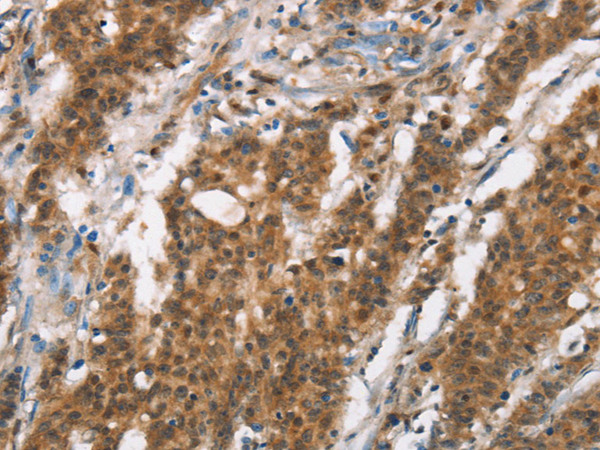

IHC positive control: |

Human gastic cancer and Human thyroid cancer |

IHC Recommend dilution: |

50-200 |